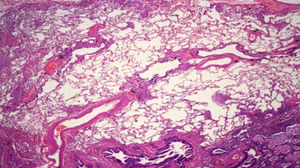

Biopsia pulmonar quirúrgicaEs la prueba que da el diagnóstico definitivo cuando en la TACAR no se observa un patrón de certeza típico de NIU. El patrón histológico de NIU viene recogido en la figura 7.